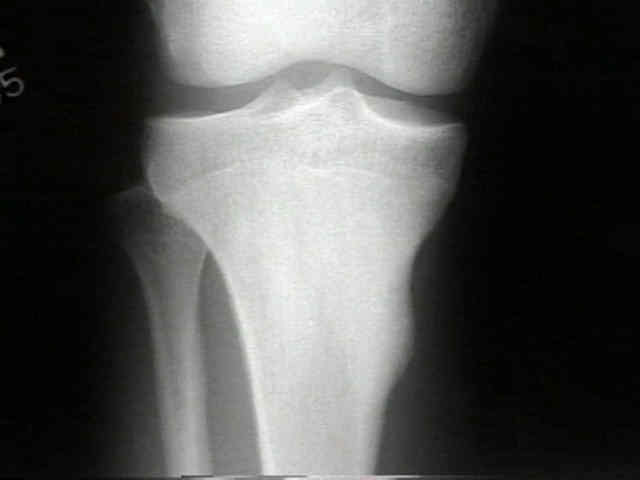

Radiografías:

La lesión característica es un pequeño nidus rodeado de hueso denso reactivo, sin embargo,  puede ser difícil de ver en las radiografías.

El nidus es casi siempre radiolucente oval de sólo 3-5 mm de diámetro rodeado por una   zona reactiva desproporcionadamente grande y densa. El tejido real del tumor es el nidus, y se deben identificar para poder clasificar la lesión con el diagnóstico de osteoma osteoide.

Aunque normalmente se localiza en la cortical, los nidus pueden ocurrir en la región subperióstica y endostal.

Hay que cuatro características diagnósticas que ofrece el osteoma osteoide. La lesión es redonda u ovoide y normalmente es menor de un centímetro de diámetro. El centro de la masa es homogéneamente densa, y hay una zona delgada, de uno a dos-milímetros radiolucente periférica. En un estudio, aproximadamente el 50% de 448 osteomas osteoide mostró todos estos rasgos. Los huesos normalmente involucrados eran el fémur (135 de 448, 30%), la tibia (121 de 448, 27 %), el húmero (cuarenta y cinco de 448, 10%), la columna (treinta y uno de 448, 7%), y el talus (dieciocho de 448, 4%). En los huesos largos, la lesión es normalmente intracortical; en la columna, involucra normalmente, los elementos posteriores ( Fig. 1A y Fig. 1B). El osteoma osteoide del talus normalmente se encuentra más en el cuello que en el cuerpo.

El osteoma osteoide tiene una región oval bien demarcada de producción de hueso característicamente separada de tejido reactivo circundante del huésped o hueso laminar. No hay ninguna infiltración de la lesión en el hueso normal. El propio nidus contiene osteoide o tejido óseo, o ambos. No hay ninguna evidencia de tejido cartilaginoso. El centro del nidus normalmente es más maduro y mineralizado y por consiguiente tiene una apariencia radio opaca en las radiografías.